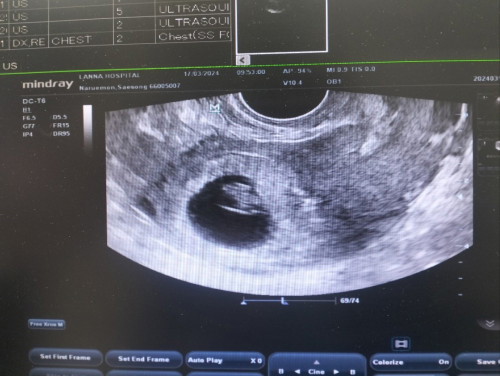

อัลตราซาวด์

จากครั้งที่แล้วไม่เจอน้องแต่ตอนนี้เจอน้องแล้วนะค่ะ

กี่วีคแล้วคะ หัวใจน้องเต้นยังแม่

7วีคจ้า